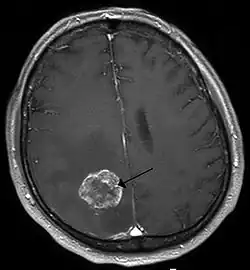

Brain imaging (neuroimaging such as CT or MRI) is needed to determine the presence of brain metastases.[6] In particular, contrast-enhanced MRI is the best method of diagnosing brain metastases, although primary detection may be done using CT.[10] Positron emission tomography (PET) is usually not considered suitable for imaging of brain metastases, because the most frequently used PET-radiotracer, 18F-FDG, does not only accumulate in the tumor but is naturally taken up by normal brain tissue, usually resulting in insufficient tumor-to-background contrast. PET-imaging of brain metastases is however feasible using alternative radiotracers, such as the Gallium-68 labeled peptide 68Ga-Trivehexin,[13] a tracer targeting the tumor cell surface protein αvβ6-integrin. 68Ga-Trivehexin demonstrated high uptake in a brain metastasis of tonsil carcinoma but no uptake in the surrounding healthy brain tissue, enabling a delineation of the brain metastasis (see image).[14]

In addition to imaging, biopsy is often recommended to confirm diagnosis.[6] The diagnosis of brain metastases typically follows a diagnosis of a primary cancer.[10] Occasionally, brain metastases will be diagnosed concurrently with a primary tumor or before the primary tumor is found.